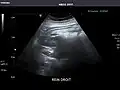

Renal ultrasonography

Ultrasound scan of a kidney (right side)

Ultrasonography of the kidneys is essential in the diagnosis and management of kidney-related diseases. The kidneys are easily examined, and most pathological changes in the kidneys are distinguishable with ultrasound.[7]

Kidneys: Right and left kidneys measure 11.5 cm and 12 cm in length respectively. No hydronephrosis. Small left lower pole kidney cyst.